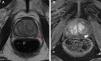

Síntesis de evidenciaLos tumores de bajo riesgo, PSA<10-15, Gleason≤6, junto con las biopsias guiadas apoyadas con la resonancia magnética nuclear (RMN) y la unilateralidad deben ser el estándar para dicha selección. Existen dudas sobre la conveniencia de la terapia focal en los casos de bilateridad o aquellos de Gleason 3+4 o PSA>15.

Summary of evidenceFocal therapy standardized criteria must be: low risk tumors, PSA<10-15, Gleason score≤6, and unilateral presentation all supported by image-guided biopsy and nuclear magnetic resonance (NMR). There are doubts about the suitability of focal therapy in cases of bilateralism or in those with Gleason score 3+4 or PSA>15.